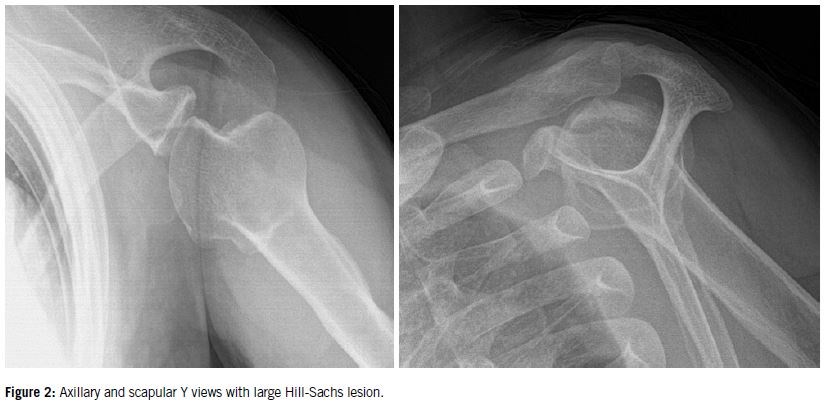

Anteroposterior, Grashey, scapular Y, axillary, West Point, or Bernageau views are among the plain radiographs that can be used to detect fractures, glenoid rim injuries, or a Hill-Sachs lesion (Figure 2). Following the initial evaluation, advanced imaging is utilized to completely describe osseous and soft tissue injuries. Soft-tissue lesions (Bankart, SLAP, HAGL) and any related rotator cuff rupture can be seen on magnetic resonance imaging (MRI), frequently with contrast. After the acute phase is over and the pain and swelling have subsided, an MRI is usually conducted. The gold standard for measuring the loss of glenoid bone is computed tomography (CT). For surgical planning, 3D CT reconstructions aid in visualizing bone abnormalities.